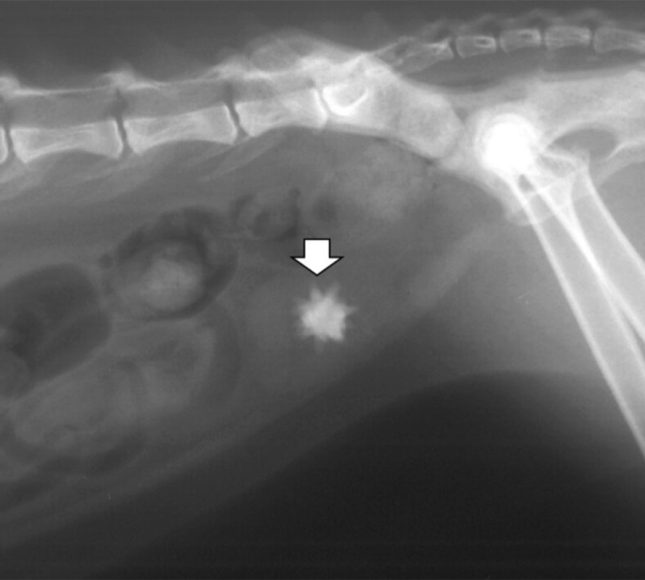

შარდკენჭოვანი დაავადება ეწოდება მდგომარეობას, როდესაც ჩვენი კატის ორგანიზმში, მის შარდსასქესო სისტემაში, კენჭები (კალკულები) წარმოიქმნება. საწყის ეტაპზე, სანამ ეს კენჭები პატარაა, ორგანიზმში მათი პოვნა ძალიან რთულია. გარდა ამისა, ისინი დისკომფორტსაც არ ქმნიან. ანუ, ამ ეტაპზე დაავადების დიაგნოსტიკა, შეიძლება მხოლოდ შემთხვევით – თუ სხვა მიზეზით მიხვედით ულტრაბგერით გამოკვლევაზე (ექოსკოპიაზე) და შარდის ბუშტში ქვიშა აღმოჩნდა.

როდესაც კენჭები დიდი ხნის წარმოქმნილია, მათი დანახვა უკვე ადვილად შეიძლება. როგორც წესი, ამ ეტაპზე ცხოველი იწყებს ხშირად ჩაცუცქვას, შარდვას, კვნესას და ამ გზით გაჩვენებთ თავის მდგომარეობას. ამ დროს თქვენ უნდა მიხვდეთ, რომ თქვენს შინაურ ცხოველს რაღაც რიგზე ვერ აქვს.

თუ ექიმები ხედავენ, რომ შარდის ბუშტი მთლიანად სავსეა და შარდი საერთოდ არ გამოიყოფა, მაშინ ყენდება კათეტერი. ეს ზოგჯერ ნარკოზის ქვეშ კეთდება, ზოგჯერ უბრალოდ ტკივილგამაყუჩებელი ინექციების ქვეშ. ძირითადად, სამი დღით დგება ეს კათეტერი შარდსადენში. ცხოველი დადის პამპერსით, უტარდება სხვადასხვა მკურნალობა, აუცილებლად უკეთდება წვეთოვანი გადასხმები და სამი დღის შემდეგ კათეტერი იხსნება. თუ თქვენს ცხოველს ყველაფერმა გაუარა, კენჭები თუ ქვიშა გამოვიდა, მაშინ მკურნალობა გრძელდება კათეტერის დაყენების გარეშე.